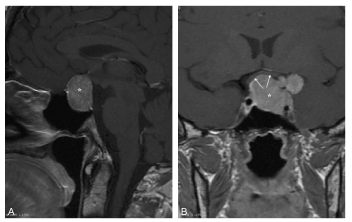

Le macroadénome se traduit par une masse intra- et extrasellaire de plus de 10 mm comprimant les structures adjacentes (figure 51.2).

Fig. 51.2. Macroadénome hypophysaire.

IRM en coupes sagittale (A) et frontale (B) pondérées en T1 après injection de gadolinium. Masse intra- et extrasellaire comprimant les structures adjacentes, avec déplacement du chiasma optique vers le haut (flèches). À noter sur la coupe frontale l’extension latérale gauche de ce macroadénome dans le sinus caverneux.

Source : CERF, CNEBMN, 2022.

Une extension suprasellaire est fréquente, pouvant comprimer le chiasma optique. Cette extension est bien analysée en coupes frontales et donne un aspect caractéristique en « brioche ». Une extension latérale est possible dans le sinus caverneux.